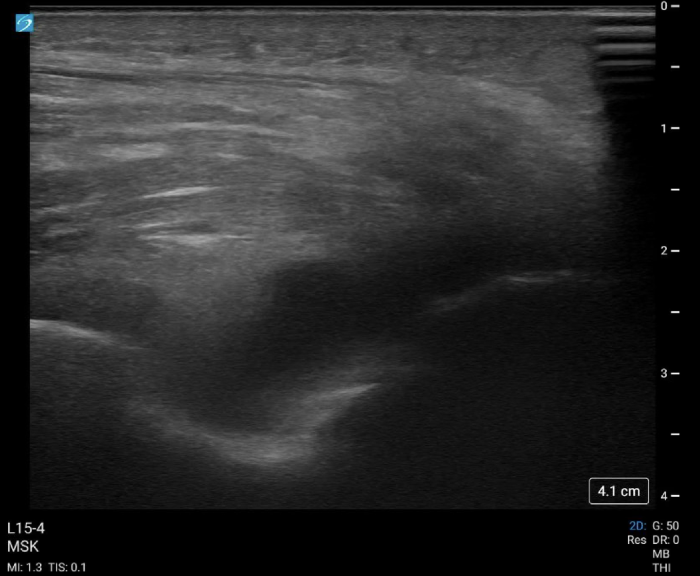

It is also imperative to remove all identifiers from the ultrasound image themselves, beyond the medical record number. For example, the date and time of the POCUS study and information about the performing user and the institution where the ultrasound was performed should be removed. Further, did you know that when using the ‘crop’ feature in PowerPoint or Keynote, the original ultrasound clips with the patient information can still be retrieved? Hidden data within the ultrasound image files themselves lives ‘metadata’, which can also be tracked back to the patient. There are numerous editing softwares available; we recommend first running all of your ultrasound clips through the ‘ClipDeidentifier’ tool available on the Core Ultrasound website. This tool allows you to crop multiple clips from the same series at once and removes the hidden ‘metadata’ from the images themselves. The generated cropped images from ClipDeidentifier are generally safe to distribute without exposing the patient’s PHI. Remember– protecting the patient's information is ultimately your responsibility!

Case #2: “A 92-year-old male with a history of alcohol use, gout (last episode in May 2021), hypertension well-controlled with hydrochlorothiazide, presented to the University of Wisconsin ED with right elbow pain and swelling. Ultrasound is shown below:”

Try instead: “An elderly male with a history of alcohol use, gout, and well-controlled hypertension, presented to the emergency department with elbow pain and swelling. Ultrasound is shown below:”